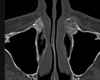

Masculino, 12 anos

Síndrome da sincondrose isquiopúbica assimétrica (Doença de Van Neck-Odelberg)

Variante da normalidade (em geral assintomático)

Crianças

Alargamento e radioluscência na sincondrose isquiopúbica, que simula neoplasias, infecção;